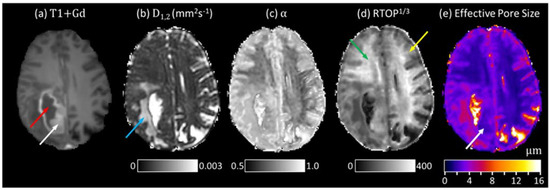

3.2. Quasi-Diffusion Imaging of Brain Tumour